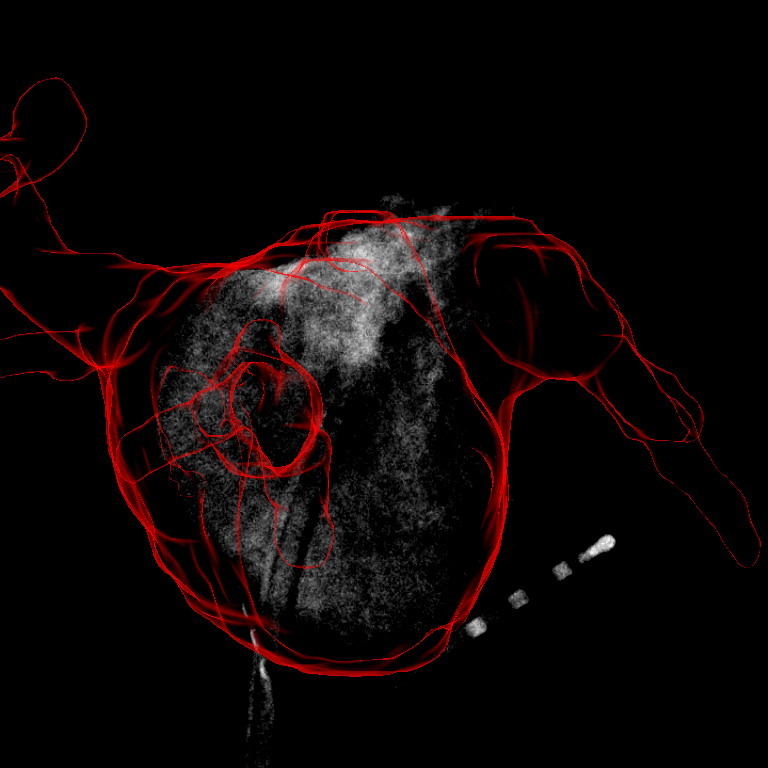

The evaluation results are presented in TABLE I. The overall inter-user-variablity observed in the manual registrations was 3.22.3 mm. Considering all sequences, and gave significant better results when they are combined with . Also the performance of was significantly better than , and . Compared to other measures, gave significantly worse results. An example for a result is given in Figure 4.

The image preprocessing takes 0.5 s on an Intel Xeon E3 with 3.4 GHz and 16 GB RAM. The evaluations of the similarity measures were performed completely on the GPU. On an NVIDIA GeForce GTX 660 the evaluation of , and took 1.8 ms for a given translation and 13.43.7 ms for . The whole registration for a single frame takes 2.9 s for and and 21.55.9 s for . For a combination with it takes 5.8 s and 27.15.9 s, respectively.